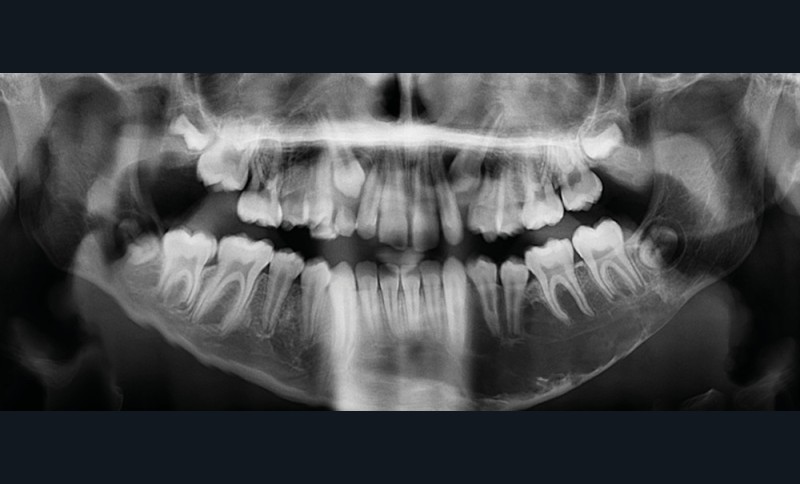

Il existe une zone ostéolytique unique, aux contours extrêmement fins, évidant la branche horizontale de la mandibule, et dont la limite supérieure est mieux marquée et dite « circinée », contournant les racines dentaires.